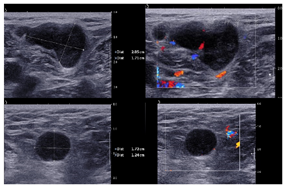

皮肤肿物及引流区淋巴结超声提示:右侧会阴部及肛门偏左侧皮下软组织内分别见混合回声区,大小25 mm×11 mm,13 mm×9 mm,形态不规则,边界不清晰,内部回声不均匀。周边皮下软组织肿胀,回声增高。病灶内部及周边可见血流信号。剪切波弹性成像提示病灶较周围组织硬(图2、图3)。双侧腹股沟区可见数个低回声区,较大者大小28 mm×17 mm,形态不规则,边界尚清晰,内部回声不均匀,皮髓质分界不清,未见淋巴门样结构。内部见血流信号(图4)。右侧会阴部及肛门偏左侧皮下软组织内实性结构,恶性病变可能性大。双侧腹股沟区实性结构,考虑异常淋巴结。